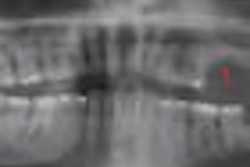

"Orthodontic radiographs carried out in radiological clinics are essential for diagnosis, planning, and control of orthodontic treatment," researchers from Federal University of São Paolo wrote. For example, they noted, both a lateral cephalometric x-ray and panoramic x-ray should be obtained from all patients prior to treatment to enhance the diagnosis and treatment plan.

"Frontal cephalometric analysis is also a valuable complementary examination in establishing the correct diagnosis and orthodontic planning," they wrote. "At present, lateral and frontal cephalograms are considered mandatory in orthodontic therapy."

The study comprised 18 healthy volunteers (six male, 12 female) with a mean age of 14.2 years who were referred to the Methodist University of São Paulo for orthodontic therapy. All participants underwent lateral and frontal cephalometric x-rays and panoramic dental radiography prior to orthodontic treatment. Oral mucosa cells were collected immediately before x-ray exposure and 10 days afterward.